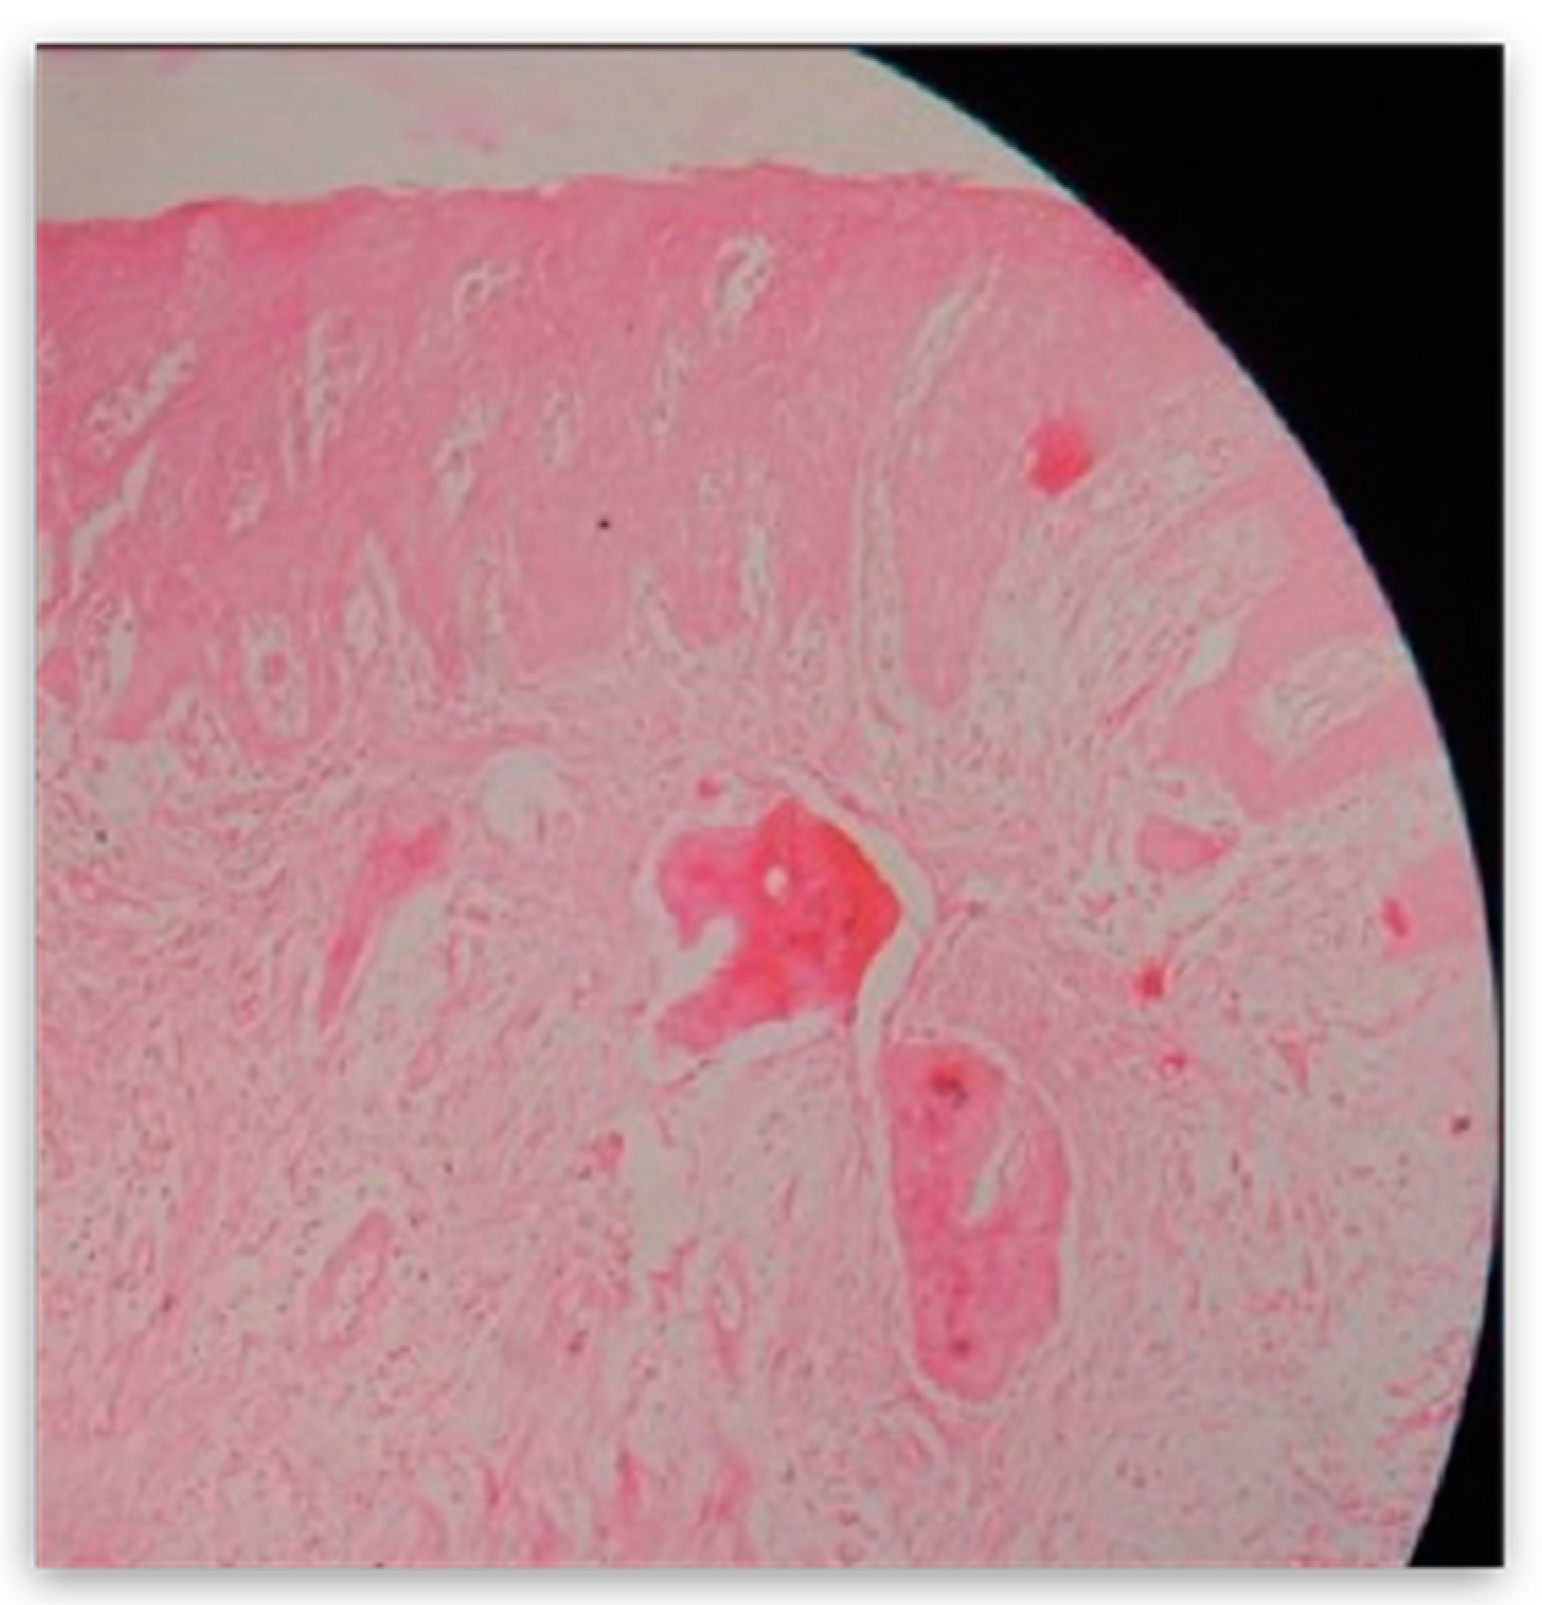

The mass was then sent for pathohistological (PHD) analysis, which showed that the mass has a reactively changed multilayered epithelium with abundant mononuclear linear inflammatory infiltrate underneath. There were no elements of Lichen. Fragments resembling cemento-osseous lacunae were found inside the thick fiber stroma. A restricted area with clusters of hemosiderin and gigantocellular cells was found in the middle of the sample. Interestingly, a small salivary gland with multiplied intra- and interlobular tissue with widened performing ducts was found in the sample. The outer edges of the sample also contained part of the mucocele wall (Figure 8).

Figure 8. Histological finding of the preparation at magnification 4×.